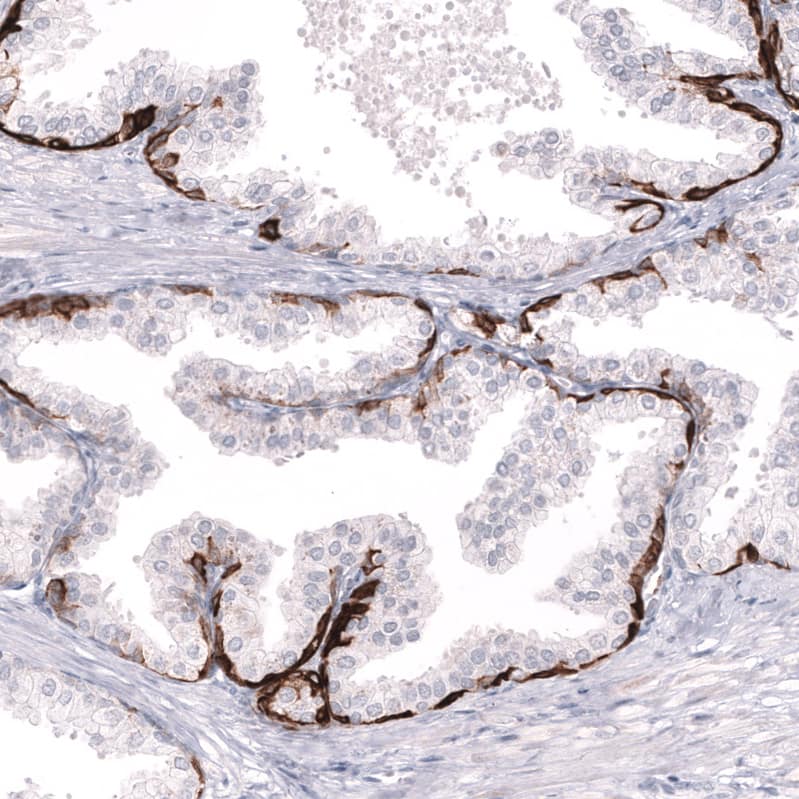

Staining of human prostate shows strong cytoplasmic positivity in basal layer of glandular cells.